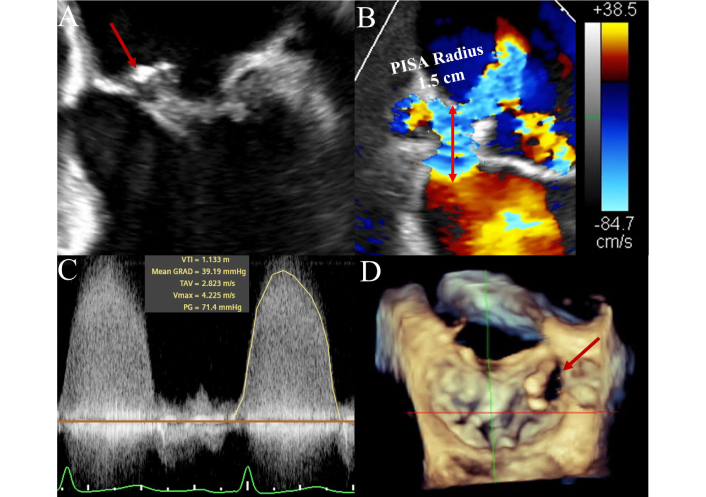

In NVE, TTE performance is highly dependent on image quality and pretest probability. It provides a high negative predictive value when technically adequate in low-risk patients. However, in patients with intermediate or high clinical suspicion, TEE is usually required to confirm or exclude IE. TEE demonstrates excellent sensitivity (up to 95%) and specificity (~90%) for vegetations, abscesses, and leaflet perforation. Both TTE and TEE can produce false negatives if vegetations have embolized or are very small. When clinical suspicion remains high after negative TTE, or when surgical intervention is anticipated, TEE is strongly indicated [1, 8]. Native mitral valve IE with perforation and severe regurgitation is depicted in Figure 2.

Mitral valve native infective endocarditis on transesophageal echocardiography. Figure 2 illustrates a case of a native mitral valve infective endocarditis in a 56-year-old female manifesting as a large vegetation on transesophageal echocardiography attached to the anterior mitral leaflet (AML) (Panel A: four-chamber view, see arrow) with a suspicious echo free space in the body of the AML for leaflet destruction and perforation, confirmed with color Doppler in the same view. Red arrow pointing to Doppler flow across the valve (Panel B). Large proximal isovelocity surface area (PISA) radius (1.5 cm) with Nyquist limit lowered to 38.5 cm/s. Panel C represents continuous wave Doppler through the leaflet perforation, with findings confirming severe regurgitation through this orifice. Panel D represents three-dimensional multiplanar reconstruction of the mitral valve (3-D MPR, surgeon’s view), with the red arrow highlighting the perforation of the AML medially.